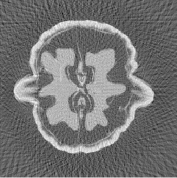

We use the Shepp-Logan phantom, available, for instance, in the Matlab Image Processing toolbox (see Figure 1). The phantom is sized , with . The projection data (i.e., sinogram) of the simulated phantom is corrupted by a white Gaussian process with zero mean and variance.

The reconstructions of the Shepp-Logan phantom are shown in Figure 4. Plots of the sparsity levels, as the iteration progresses, are reported in Figure 6. For the 120 projections case, the proposed approach converges in 885 iterations, while, in the 30 projections case, it converges in 301 iterations. As figure of merit, we use the relative error: the obtained values are summarized in Table 2, where we also report the values of the relative error obtained for the FBP reconstructions.